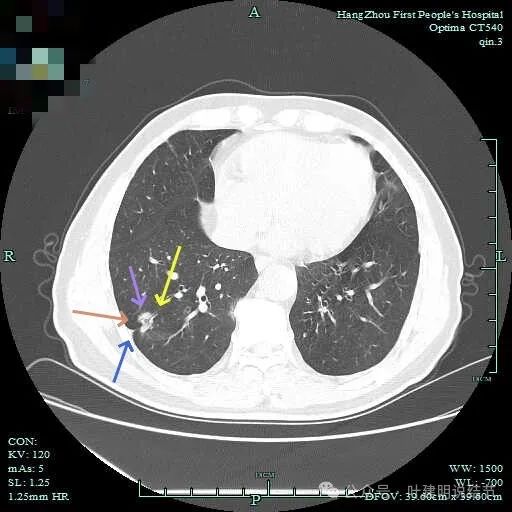

边缘毛糙有细毛刺,灶内密度不均;胸膜牵拉以及表面不平;黄色箭头示细支气管截断的样子。

血管征以及胸膜凹陷征。

轮廓与边界清,灶内有小空泡征。

多支血管进入,灶内密度不均。

胸膜牵拉,表面不平,血管进入并有异常增粗。